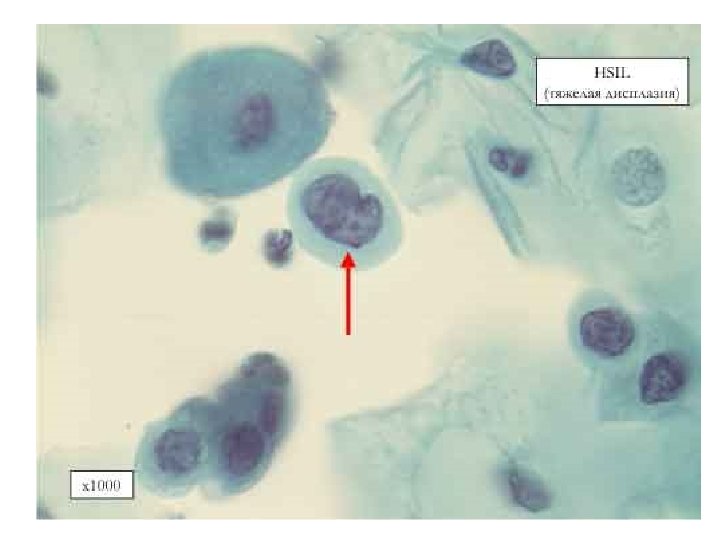

Молекулярные исследования при заболеваниях шейки матки Диагностика и прогноз развития интраэпителиальной неоплазии • p 16, p 53 • Метилирование ДНК Гены DAPK, HIN 1, MGMT, RAR-β, RASSF 1 A, SHP 1 – увеличение с увеличением степени дисплазии MGMT, RAR-β, Twist – увеличение частоты метилирования при HSIL-Cr

Результаты тестов: р16 и ВПЧ при проблемах интерпретации (ASC-US/ASCH) • В 11 из 17 наблюдений с ASC-US/ ASC-H отмечена экспрессия р16, причем в 10 из них гистологически выявлены HSIL+